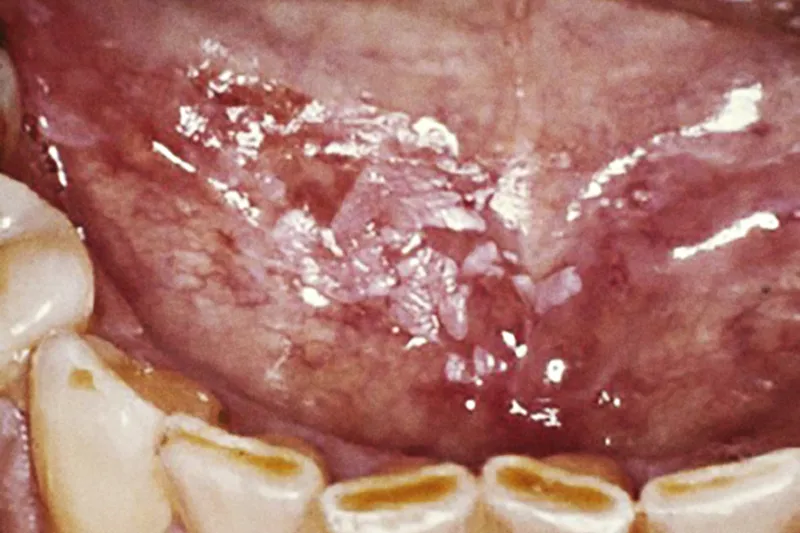

Personer, der er eller har været ramt af cancer, må ofte leve med senfølger af sygdom og behandling i mundhulen. Blandt de hyppigst forekommende senfølger i mundhulen ved kræftsygdom er mucositis, infektioner, hyposalivation/xerostomi, dysfagi og smagsforstyrrelser.

Nedenfor er angivet nogle af de mest almindelige komplikationer hos cancerpatienter og udvalgte behandlingsmetoder. Listen er ikke udtømmende.

- Mild eller moderat mucositis/komplikationer i mundhulen

- Graft-versus-host-disease Mucositis kan være et kendetegn for kronisk graft versus hostsygdom (GvHD) hos cancerpatienter. En opløsning af steroider kan anvendes som behandling, og yderligere behandling kan omfatte opløsninger af steroider i kombination med andre lokale eller systemiske immunsuppressive lægemidler. Denne behandling skal varetages af en speciallæge i hæmatologi. For tandplejepersonalet kan opgaven være at henvise til en sådan på baggrund af en mistanke om GvHD.